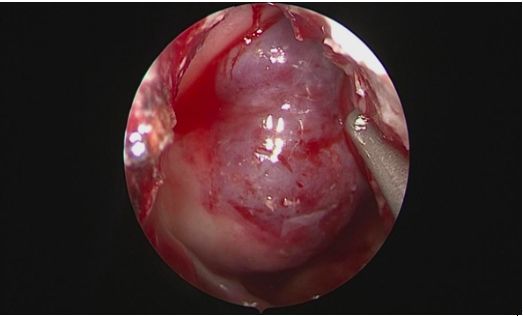

(神经内镜下充分显露鞍底)

患者为中年藏族男性,39岁,一年前因垂体瘤在四川大学华西医院西藏成办分院行经额部开颅垂体瘤切除术,术后复发遂到昌都市人民医院外二科就诊。在昌都市人民医院党委、外二科余正强主任以及重庆市“组团式”医疗援藏队的大力支持下,现任外二科副主任的重医大附二院神经外科陈晋副教授带领张琪医生,围绕神经内镜辅助下经鼻蝶窦垂体肿瘤切除的适应症、具体操作及术后护理康复等方面,在科室全体医护人员参与下进行了充分讨论并制定了详细的预案。经过周全准备,在昌都市人民医院麻醉科余中良主任、来自重庆三峡中心医院麻醉科的援藏队员陈吕富副主任亲自施行麻醉下,陈晋副教授与张琪医生顺利进行了神经内镜辅助下经鼻蝶入路垂体肿瘤切除术,术中全切肿瘤,出血约50ml。护理团队积极指导康复训练,术后仅七天患者便康复出院。